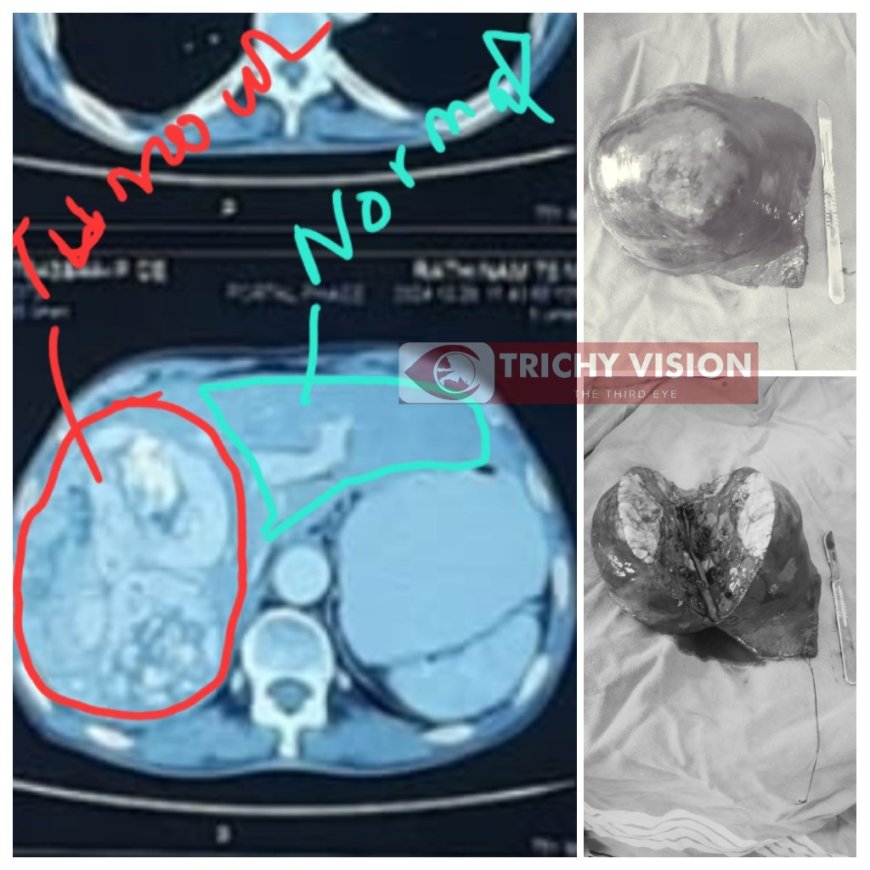

திருச்சி அரசு தலைமை மருத்துவமனை டீன் குமரவேல் கூறுகையில்…. திருநெடுங்குளத்தை சேர்ந்த 75 வயது முதியவர் ஒருவர் கடுமையான வயிற்று வலியுடன் மருத்துவமனைக்கு அழைத்து வரப்பட்டார். திருச்சி அரசு மருத்துவமனையில் மேற்கொண்ட பல்வேறு பரிசோதனைகளில் அவரின் கல்லீரலின் மேற்பகுதியில் கட்டி இருப்பது உறுதி செய்யப்பட்டது.

இதயம், நுரையீரல், மயக்கமருந்து நிபுணர்கள் உள்ளிட்ட குழுவினர் அளித்த லேப்ராஸ்கோப்பி சிகிச்சை மூலம் கல்லீரலின் வலது பக்கத்தில் இருந்த கட்டி 60 சதவீதம் கல்லீரலுடன் சேர்த்து அகற்றப்பட்டது. இதயம் வெளியேற்றும் ரத்தத்தில் 25% கல்லீரலுக்கு (1200 மிலி) செல்வதால் மிகவும் கவனத்துடன் நவீன கருவியை பயன்படுத்தி அனுபவம் வாய்ந்த மருத்துவர்கள் இந்த சிகிச்சையை மேற்கொண்டனர்.

டீன் குமரவேல், மருத்துவ கண்காணிப்பாளர் உதயஅருணா, துணை கண்காணிப்பாளர் அருண்ராஜ் ஆகியோர் மேற்பார்வையில் டாக்டர்கள் கண்ணன், சங்கர், ராஜசேகரன், கார்த்திகேயன், இளங்கோ, இளவரசன் ஆகியோர் அறுவை சிகிச்சை செய்தனர். இந்த அறுவை சிகிச்சையில் கல்லீரலின் மேற்பகுதியில் 1.5 கிலோ எடையுள்ள கட்டி அகற்றப்பட்டது குறிப்பிடத்தக்கது.